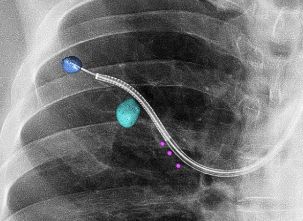

Using light instead of x-ray, Tilo Kölbel at

#LINC2020 shares his first experience as a limited edition site, using@PhilipsHealth#FORStechnology for#FEVAR! 3D navigation. Device visualization. No radiation.#FutureofIGTpic.twitter.com/Fhni4gFso1